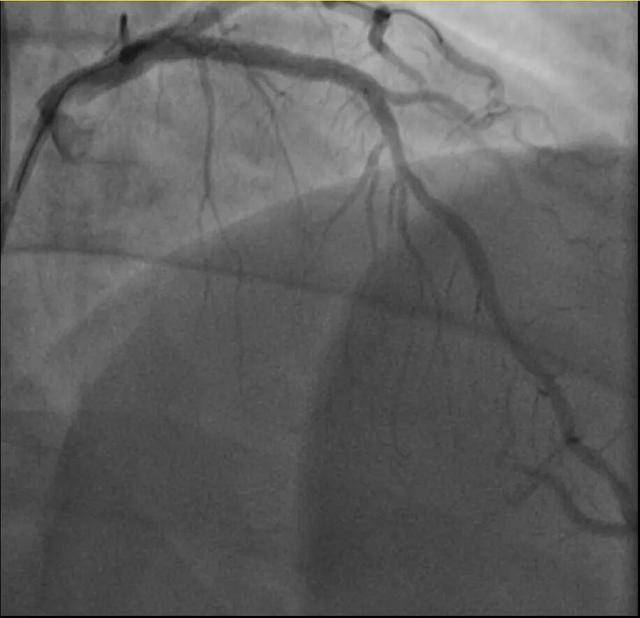

孙先生是一位羽毛球教练,身高173厘米,体重约90公斤。一年前,他因胸闷就诊,被查出心脏右冠中段、远端钙化斑块,以及前降支中段60%狭窄。尽管没有三高的危险因素,但可能有早发冠心病家族史。孙先生坚信通过运动瘦身可以扭转健康状况,因此拒绝了介入治疗,仅接受药物治疗。一年内,他的体重从96公斤减到了90公斤左右。然而,近期他在陪孩子打羽毛球时,亲自上场挥杆仅10分钟左右,就因心前区剧烈绞痛被送进了急诊。浙江医院心血管内科副主任汤益民主任医师分析,剧烈运动导致孙先生心脏的不稳定斑块破裂,造成前降支近段次全闭塞。所幸送医及时,经过紧急介入治疗,孙先生的身体险情被成功化解。

同一天,钱先生也有类似遭遇。他平时身体不错,只是血糖偏高,服药后控制不佳。周末,他和孩子爬了一座山,隔天就因突发胸骨中段压榨性疼痛被送到了急诊,最终被证实是心梗——心脏回旋支远段次全闭塞。来院时,钱先生的血糖为12.79mmol/L(正常空腹值应在3.9~6.1mmol/L),甘油三酯也超标。三高(高血压、高血脂、高血糖)是导致动脉粥样硬化的主要危险因素。在冠状动脉粥样硬化早期,血管狭窄可能并不严重,但在运动或情绪激动等情况下,心肌耗氧量增加,可能导致心梗等急性心肌缺血事件。经过汤益民团队的及时介入治疗,钱先生也转危为安。